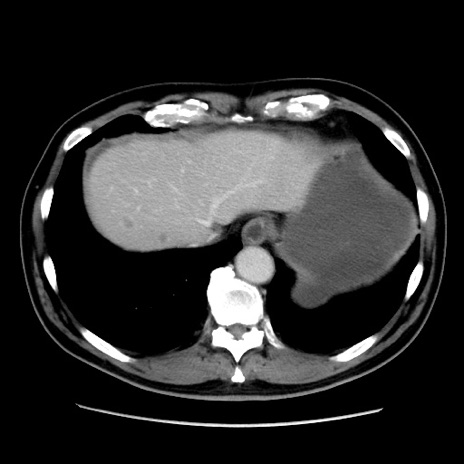

症例16(横断像)

【症例】 70歳代男性

【主訴】 腹痛、嘔吐

【現病歴】 約1ヶ月前より間欠的に腹痛と嘔吐あり、当院消化器内科を受診したところCTで多発する肝臓のLDAを指摘され、精査中であった。以降は消化器症状は安定していたが、2日前より嘔気と腹痛があり、同日より排便・排ガスが消失した。改善認めず、 本日、救急外来を受診した。

【既往歴】 大腸ポリープ切除後。

【身体所見】意識清明・会話良好、BT 36.3℃、BP 127/80mmHg、 P 80bpm、腹部:膨満あり、平坦・軟、上腹部正中および下腹部正中に圧痛あり、反跳痛なし、筋性防御なし。

【データ】WBC 7200、CRP 0.77